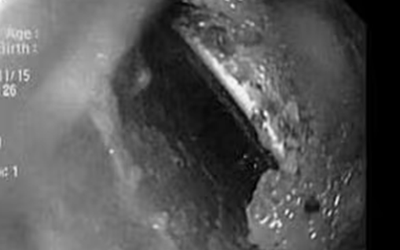

Người đàn ông 41 tuổi đau dữ dội, bác sĩ "sốc ngang" thấy con lươn dài 50cm trong bụng

Sức khỏe Thứ 2, 25/05/2026 | 02:00

Đau bụng dữ dội và rơi vào sốc nhiễm trùng, người đàn ông ở Đồng Nai khiến bác sĩ bất ngờ khi phát hiện một con lươn dài hơn 50cm đã xuyên thủng trực tràng, chui vào ổ bụng.